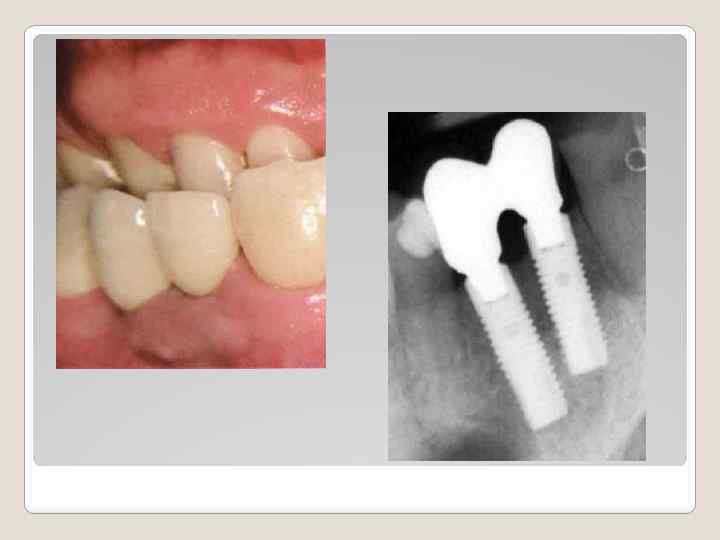

Профилактика атрофии альвеолярного отростка с помощью материала Easy-graft ® во фронтальном участке верхней челюсти (клинический случай). В клинику обратился пациент – мужчина в возрасте 38 лет, с жалобами на отлом коронковой части 23 зуба, подвижность 22 зуба и болезненность при надкусывании в этой области верхней челюсти. 22 зуб, пролеченный эндодонтически, имел 2 степень подвижности. И в проекции верхушки корня на слизистой оболочке был расположен свищ, из которого поступало гнойное выделение. 23 зуб был сломан на 3 мм ниже уровня десны и демонстрировал открытый канал корня зуба (Фото 1). При рентгенологическом обследовании были диагностированы две кисты в апикальных участках 22 и 23 зубов каждая размером около 10 мм в диаметре. Резорбция костной ткани начиналась в районе средней трети корней зубов (Фото 2).

Установка имплантатов и реабилитация. Через семь месяцев после заполнения дефекта остекондуктивным материалом Easy Graft® 400, наступила регенерация костной ткани. В некоторых местах еще наблюдались отдельные гранулы материала, но в большинстве объема костного дефекта отмечалась вновь регенерированная костная ткань. Удалось полностью предотвратить атрофию альвеолярного отростка в области удаления корней зубов. Были установлены имплантаты, на которых были зафиксированы две, металокерамические коронки. У данного пациента отмечается глубокий прикус и наличие бруксизма, поэтому небная поверхность коронок керамикой не покрывалась. Контрольные наблюдения, проведенные через 3. 5 месяцев после фиксации коронок продемонстрировали хорошие клинические результаты (Фото 5 и 6). Отмечается стабильное состояние мягких тканей. На рентгенограмме видна хорошая остеинтеграция между имплантатом и вновь сформированной костной тканью.